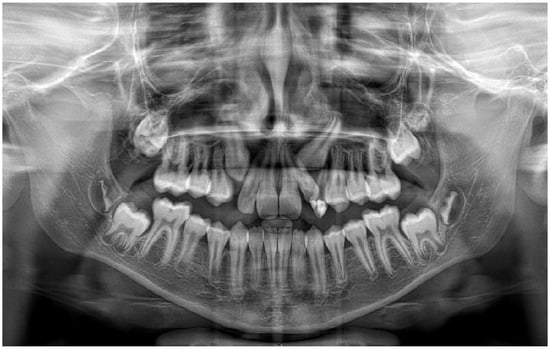

A panoramic radiograph and cone beam computed tomography (CBCT) showed a well-defined unicystic radiolucency extending from the left maxillary second incisor to the primary second molar on the same side. The permanent canine was impacted toward the maxillary sinus, and the root of the second incisor was tilted mesially by the lesion. Another radiolucency extended from the left lower lateral incisor to the primary second molar. Hypodontia of the permanent premolar was noted. The lesion was in contact with the inferior alveolar nerve [Figure 1].

Figure 1. Preoperative panoramic radiograph of a ten-year-old boy showing unicystic radiolucencies on the left side of the maxilla and mandible.